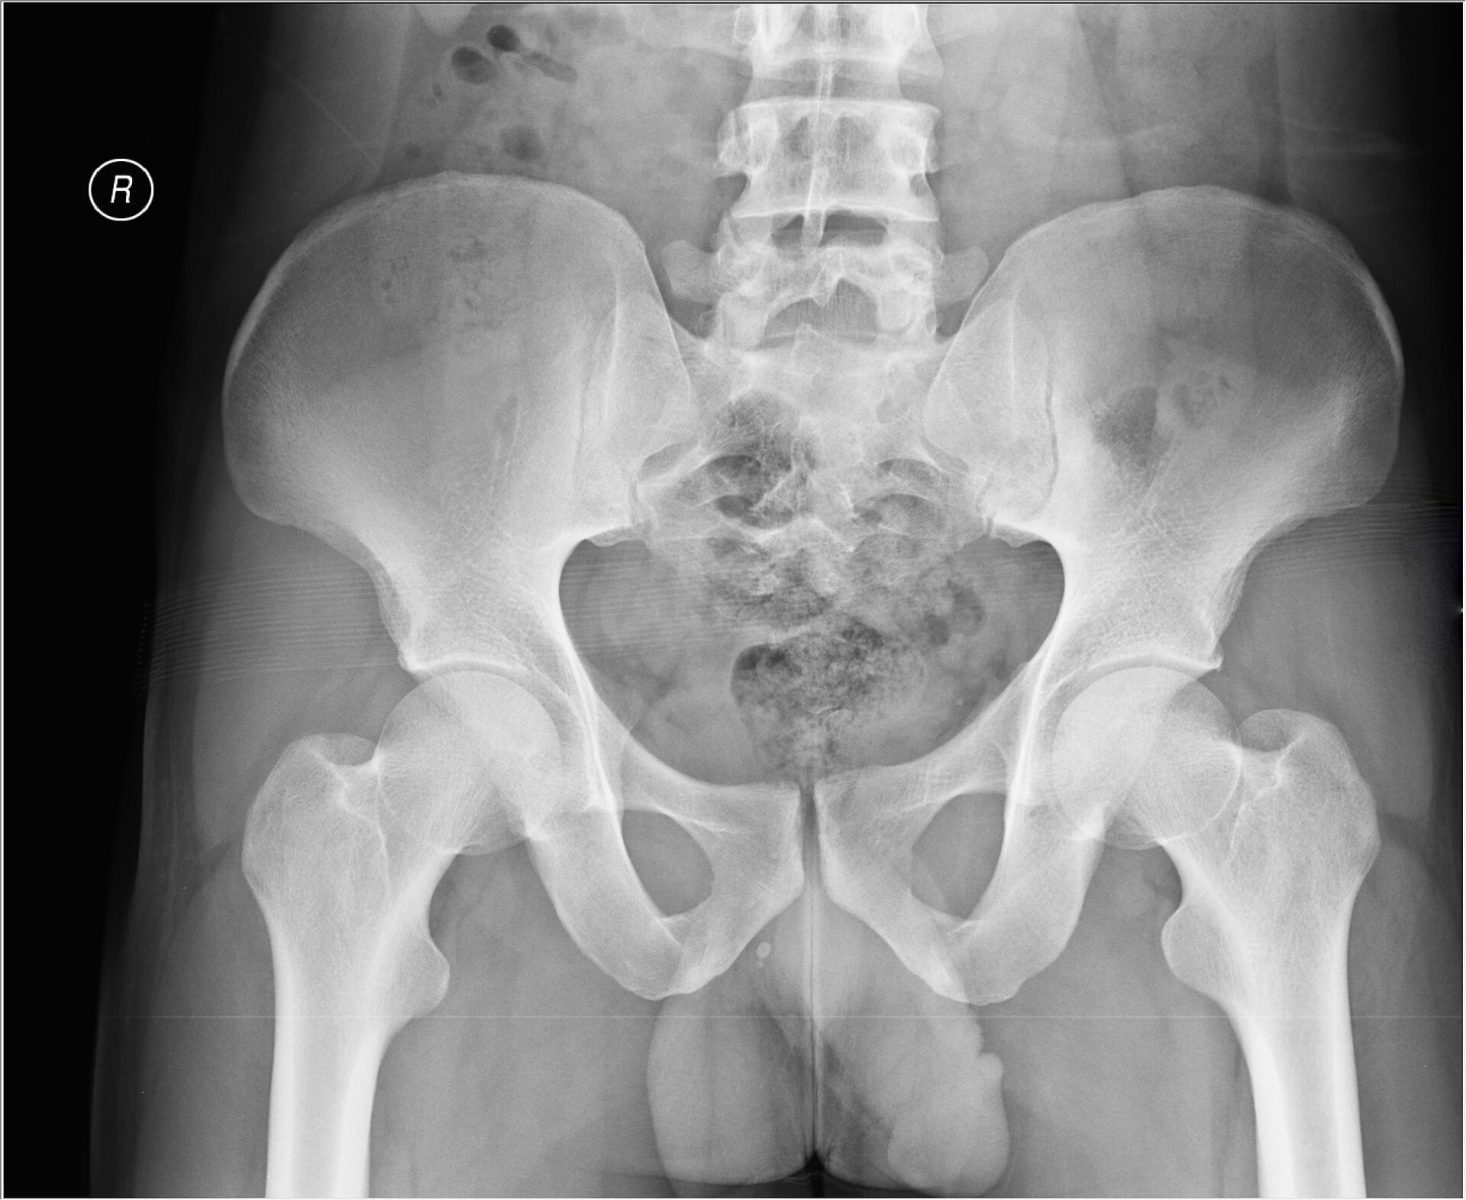

![]() |

| Normal ve artrit gelişmiş hastalara ait kalça filmleri | |